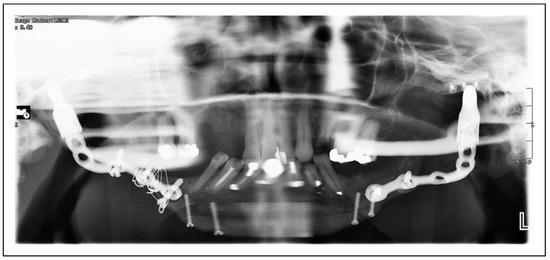

Bilateral TMJ Replacement With Complete Replacement of the Mandible, Patient 8